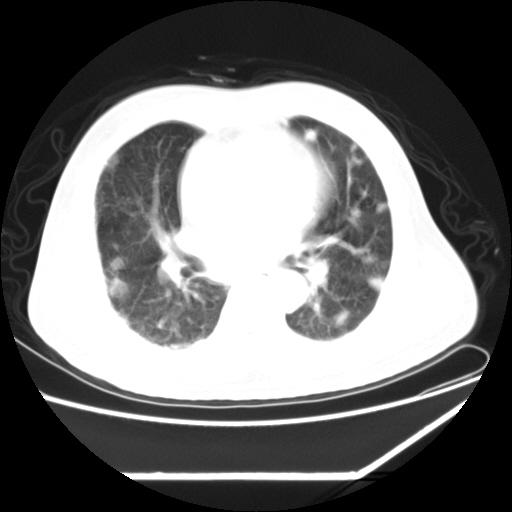

男,57,畏寒,发热

双肺多发结节样病灶,部分内见透光区,纵隔内见淋巴结肿大。结核临床如有畏寒,高热,白细胞增高首先考虑迁徙性肺脓肿(多是金黄色葡萄球菌感染)。

注意除外转移瘤。

1)考虑两肺感染性病变(金黄色葡萄球菌肺炎?);建议抗炎治疗后复查排除其他。2)双侧少量胸腔积液。

血源性肺脓肿

血源性肺脓肿,除外转移瘤